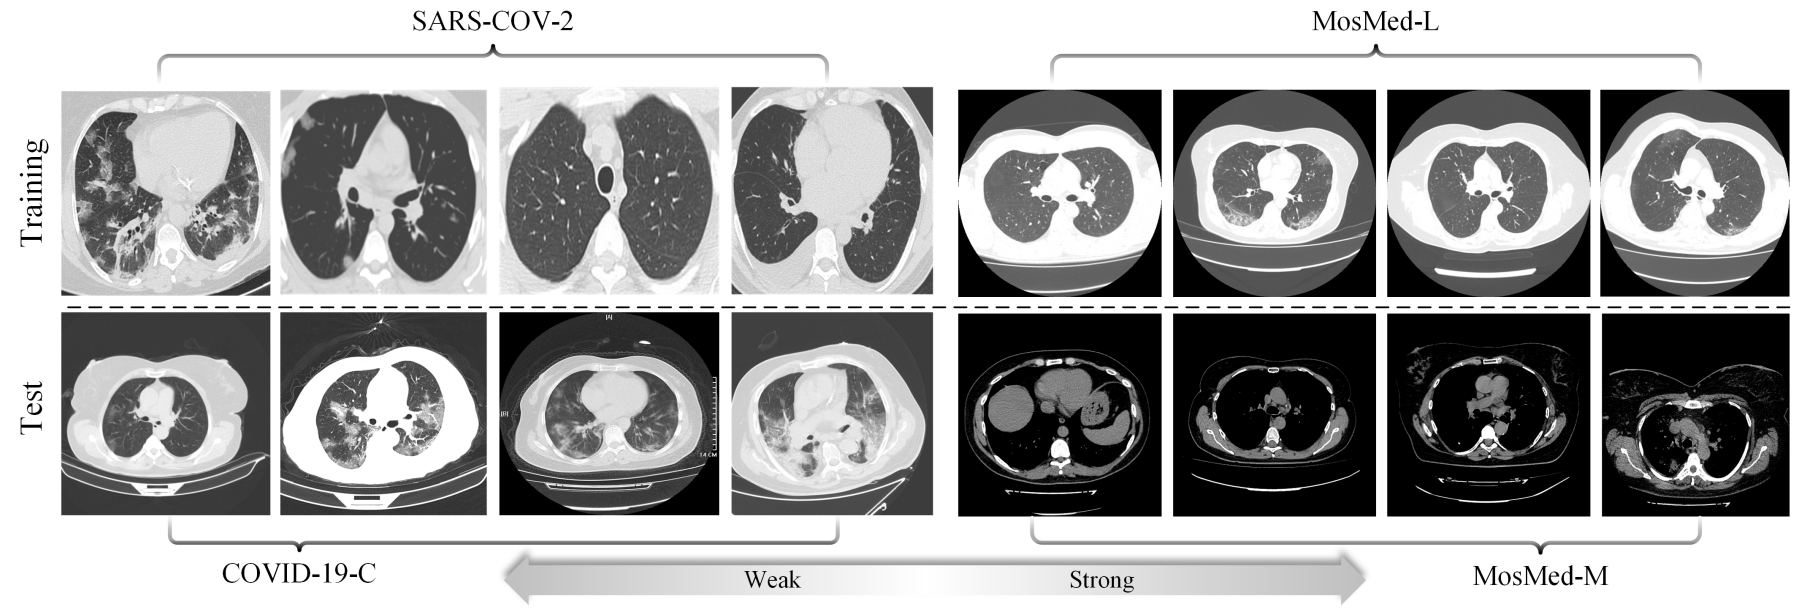

As the COVID-19 pandemic puts pressure on healthcare systems worldwide, the computed tomography image based AI diagnostic system has become a sustainable solution for early diagnosis. However, the model-wise vulnerability under adversarial perturbation hinders its deployment in practical situation. The existing adversarial training strategies are difficult to generalized into medical imaging field challenged by complex medical texture features. To overcome this challenge, we propose a Contour Attention Preserving (CAP) method based on lung cavity edge extraction. The contour prior features are injected to attention layer via a parameter regularization and we optimize the robust empirical risk with hybrid distance metric. We then introduce a new cross-nation CT scan dataset to evaluate the generalization capability of the adversarial robustness under distribution shift. Experimental results indicate that the proposed method achieves state-of-the-art performance in multiple adversarial defense and generalization tasks.